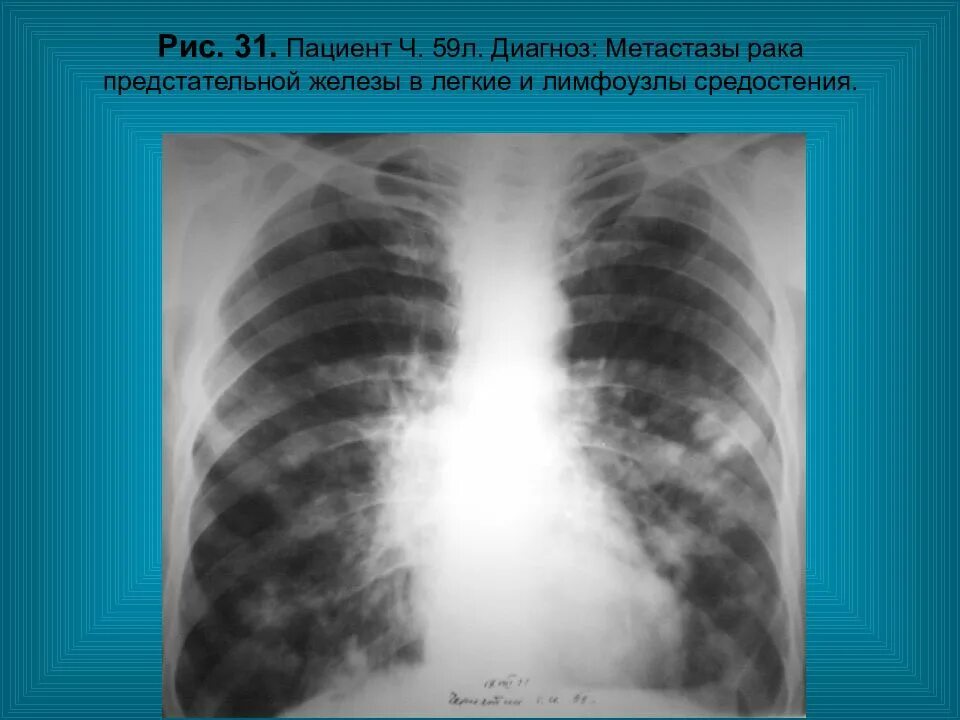

Метастазы в средостении легких